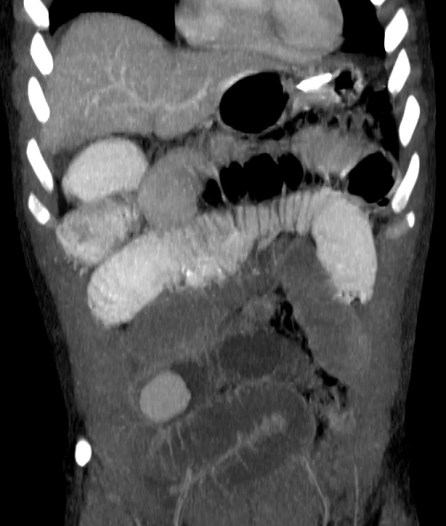

Tomografía Computarizada:

Con sensibilidad y especificidad próximas al 100%, es la técnica inicial de elección ante la sospecha de una obstruccion intestinal. Ante la sospecha firme de obstruccion intestinal, realiza un diagnóstico más preciso, aporta más información adicional y evita retrasos en el diagnóstico.

Hallazgos:

- Distensión proximal a la obstrucción mayor de 3,5 cm en el intestino delgado y mayor de 5 cm en el colon con colapso de asas distales junto con la identificación, siempre que sea posible, de la zona del cambio de calibre (zona de transición), lo que nos permite realizar con mayor seguridad el diagnóstico.

- Si se observan asas dilatadas, independientemente del grado, si no hay colapso de asas distales, el diagnóstico más probable es un íleo paralítico.

- Nivel de la obstrucción: determinado por la zona de cambio de calibre.

- En caso de obstrucción de un asa de colon existirá dilatación del colon proximal. Si la válvula es incompetente existirá también, además, dilatación de intestino delgado.

- Patrón en miga de pan en asas de intestino delgado proximal a la obstrucción (es un signo controvertido, podría indicar gravedad).

- Giro o remolino de vasos mesentérico pueden sugerir una volvulación.

- Obstrucción intestinal: cambios de calibre y dilatación de asas pre estenosis. El CT puede determinar la causa, localización y grado de obstrucción intstinal.